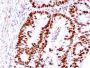

Positive Control

HCT116, MCF-7, A431 or HeLa cells. Colon Carcinoma.

Antibody target cellular localization

IF (verified), IHC, FFPE (verified), WB (verified)